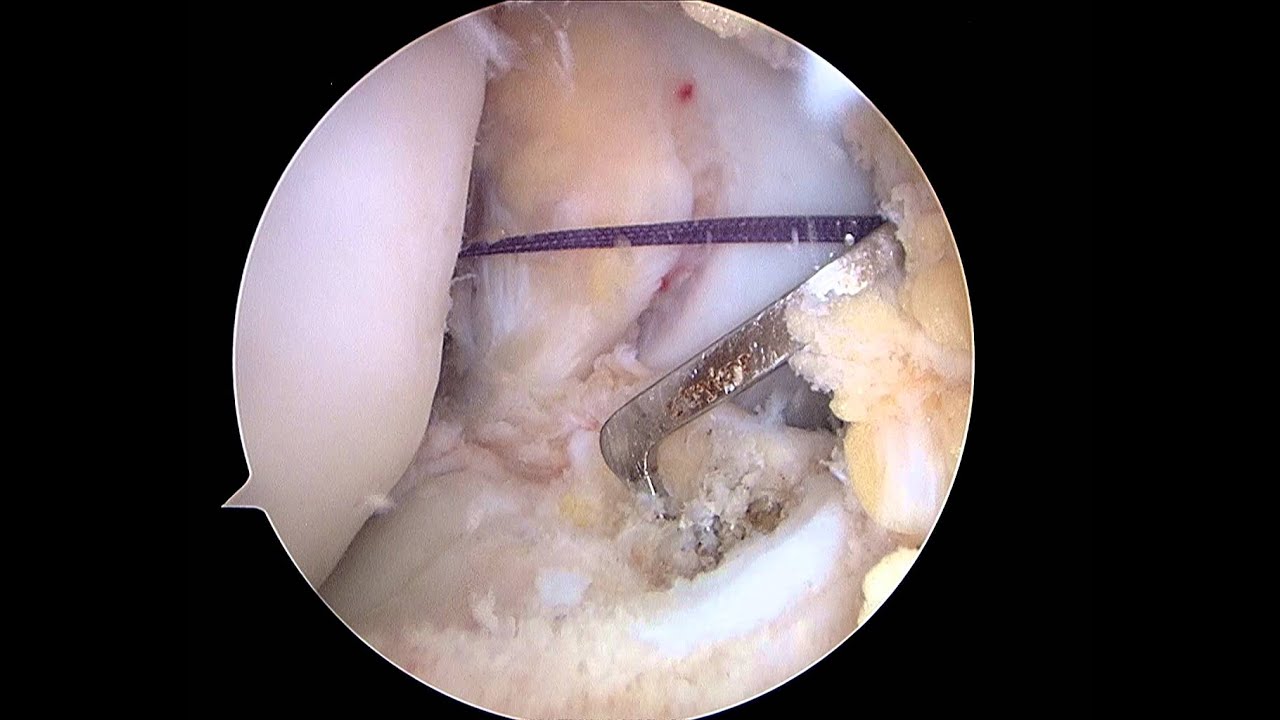

• Cirugía de menisco

Gran profesional!! Empatiza con el paciente; Se toma todo el tiempo necesario para explicar al detalle cualquier duda que se le plantee. Me inspiró mucha confianza desde el primer momento. Me operó del menisco interno y como nuevo!! Muchas gracias doctor!!

Muchísimas gracias por tus palabras y por la confianza que depositaste en mí desde el primer momento. Me alegra saber que te sentiste acompañado durante todo el proceso y que la intervención de menisco interno te ha permitido volver a encontrarte bien. Ese es siempre mi objetivo: explicar cada paso con claridad, tomar el tiempo necesario y ofrecer un tratamiento preciso y seguro para que cada paciente recupere su función lo antes posible.

Profesional fantástico, da explicaciones ilustradas con imágenes de las lesiones. Da buenos consejos para una pronta recuperación.

Muchas gracias por tu valoración y por destacar el valor de las explicaciones con apoyo de imágenes. Considero fundamental que cada paciente comprenda bien su lesión y el tratamiento propuesto, porque así la recuperación es más rápida y segura. Me alegra saber que los consejos te están ayudando en tu evolución. Seguimos a tu disposición en nuestra consulta de Traumatología y Cirugía Ortopédica en Granada para cualquier revisión o control que necesites.